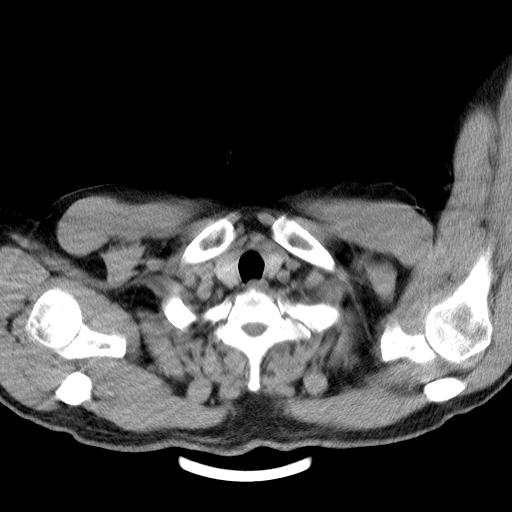

男,51岁,体检时发现右上纵隔高密度影。

右上纵隔脊柱旁圆形结节,密度均匀,边界清楚——考虑神经源性肿瘤!